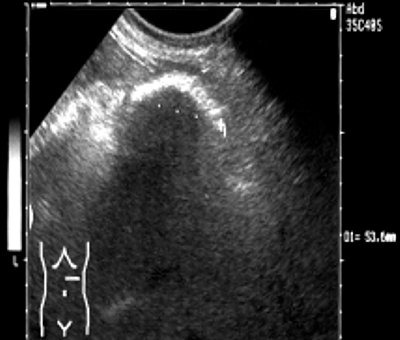

С подозрением на опухоль брюшной полости больная направлена на ультразвуковое исследование, при котором: печень в размере не увеличена, контур ее ровный, паренхима однородная. Очаговой патологии не выявлено. Внутри- и внепеченочные желчные протоки, вены, портальная вена не расширены. Желчный пузырь средних размеров, стенка его уплотнена, содержимое однородное. Поджелудочная железа нормальных размеров, структура однородная. Вирсунгов проток не визуализируется. Диаметр сечения пищеварительного тракта на уровне пищеводного отверстия диафрагмы 14,8 мм, толщина стенки 2,5 мм. В левом подреберье на уровне левой окологрудинной линии визуализируется гиперэхогенное образование 53,6 х 94,9 мм, дающее за собой акустическую тень (рис. 1). Селезенка имеет нормальные размеры и структуру. Селезеночная вена не расширена. Почки обычно расположены, не увеличены, ЧЛС - не расширена, конкрементов не определяется. Брюшной отдел аорты нормального диаметра, стенка его уплотнена. Свободной жидкости в брюшной полости не определяется.

а) Поперечное сечение.

б) Продольное сечение.